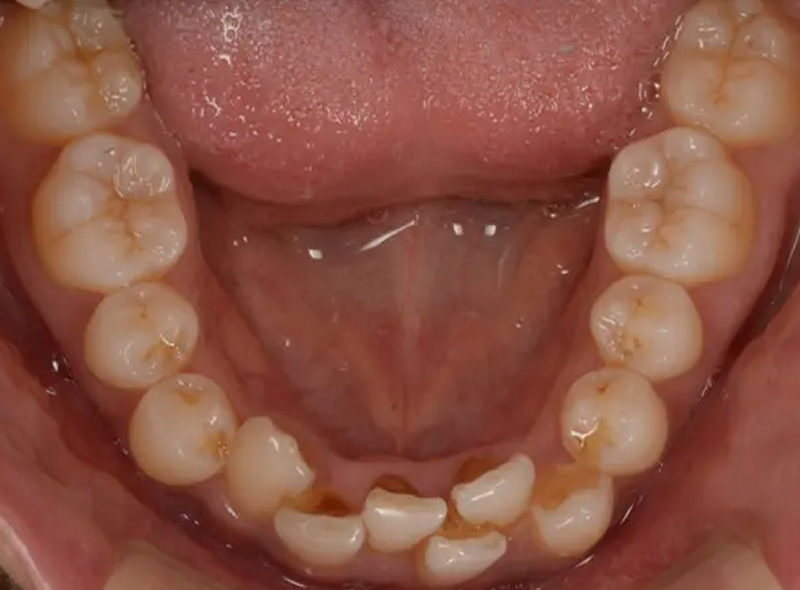

歯がガタガタに並んでいる状態を「叢生」といい、最も多い不正咬合です。八重歯も叢生の一種です。

好発部位は下顎前歯に最も多く、上顎前歯、特に犬歯は八重歯になりやすいです。

不正咬合は歯の大きさに対して顎の骨が狭いために起こることがほとんどです。歯ブラシが届きにくい箇所が生まれるため、プラーク(歯垢)が溜まりやすく、虫歯や歯周病の原因となります。